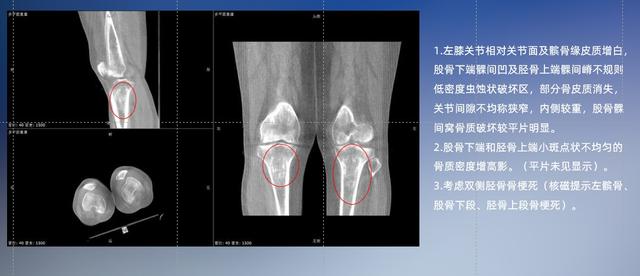

以膝关节疾病检查为例,膝关节在解剖学意义上是一种较为复杂的最大关节,由胫骨上端、股骨下端及髌骨组成。在股骨与胫骨的关节面之间存在两块半月板,分别处于内侧、外侧。膝关节的运动主要为伸、屈,在半屈位时可进行小幅度的旋外、旋内运动。随着现代人们体育生活以及肥胖的增加,膝关节疾病出现高发趋势,特别是关节磨损、膝关节炎与骨关节炎等关节退行性改变,长时间的内翻负荷会造成内侧关节软骨、骨性关节面的磨损。目前针对此类疾病的检查主要为平片下的负重位检查、CT检查以及MRI检查,相较于非负重位检查,负重位检查能更加真实反映膝关节结构中胫骨、股骨、髌骨实际对位关系和关节面的形态特征及关节间隙大小,对膝关节骨关节病诊断准确率高。

普通平片扫描与WR-3D扫描前后诊断结果对比

与此同时,数字化X线摄影技术相较于CT和MRI来说,能快速获取真实、直观、满足临床需要的影像。DR的图像具有图像层次丰富、空间分辨力高、影像边缘锐利清晰、密度分辨力高级细微结构表现出色等特点,针对膝关节解剖结构数字化X线摄影技术应用价值很高,尤其是是对骨小梁与骨皮质的显示非常清楚。在负重位状态下,数字化X线三维摄影扫描与重建,能够更好的呈现受检者关节受力改变的状态。388vip太阳集团科技创新的WR-3D动态三维数字化X线摄影技术,通过数字化X线摄影完成三维扫描并重建三维影像信息,包括MPR多平面重建、MIP重建以及VR绘制。扫描时间短,剂量相较于CT设备大幅缩减,同时成本更低,在临床诊断以及医疗方案制定中具有极大的价值意义。相较于普通平片下的负重位扫描,负重位动态三维扫描摄影技术能够避免二维状态下的组织结构重叠、密度分辨率不足、组织解剖结构难以分辨等问题,WR-3D支持多角度的动态三维摄影观察,能全面的呈现被检查部位在多个角度下三维影像信息,极大的减少了二维负重位检查的漏诊率。